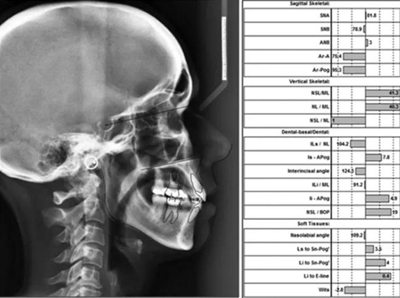

頭影測(cè)量分析,SNA角84°,ANB角6°,高角型,詳見(jiàn)下表。

患者側(cè)貌改善,下唇唇肌緊張消失,上下唇可自然閉合。磨牙及尖牙關(guān)系糾正至I類(lèi),覆合覆蓋正常。上下頜弓型糾正至卵圓形,牙弓寬度增加。頭影測(cè)量分析示SNA角81.8°,ANB角3°。頭影測(cè)量重疊圖示下頜骨向后旋轉(zhuǎn),垂直面高度略有增加。